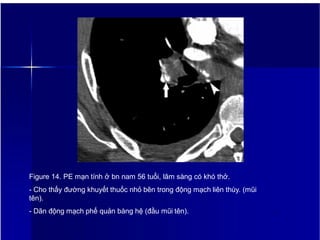

Figure 14. PE mạn tính ở bn nam 56 tuổi, lâm sàng có khó thở.

- Cho thấy đường khuyết thuốc nhỏ bên trong động mạch liên thùy. (mũi

tên).

- Dãn động mạch phế quản bàng hệ (đầu mũi tên). 17